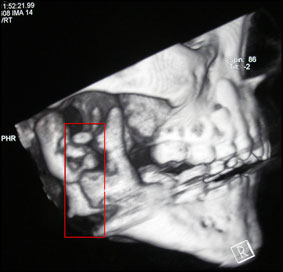

La tomodensitométrie a montré un remaniement osseux de la branche montante droite de la mandibule, lésions ostéolytiques à type de décalcification de l’os spongieux, fracture sous condylienne basse et séquestre osseux (fig. 2, 3, 4).